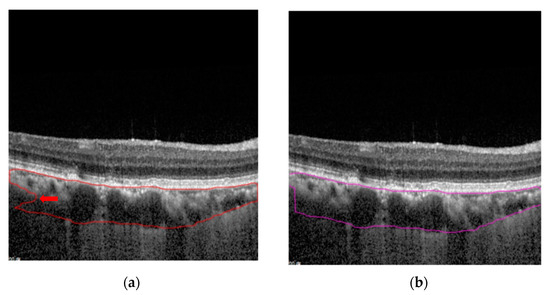

3. Results

4. Discussion